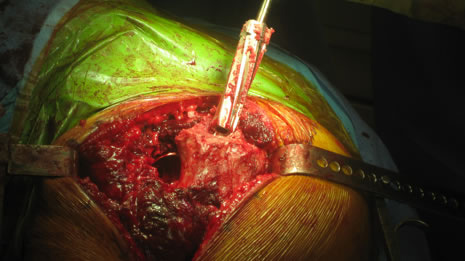

| Femoral canal preparation is begun with an opening into the femur with a starting awl, followed by a circular box chisel. |

Cup orientation and preparation is challenging and care should be taken not to penetrate the medial wall. Proper cup placement is difficult do to loss of bony landmarks. Hip abductors will be weak and joint instability is a significant concern. Lateralization of the femoral component will aid in reducing forces across the hip joint potentially reducing limp and post-operative hip dislocation.

| Pre-operative consideration was discussed on shorting the stem to avoid any potential femoral canal perforations. For this reason a special proximal modular stem “Dual-Press” design was utilized. Proximal conical reaming was done without the use of a pilot shaft along with rasping of the femoral triangle. |

Careful intra-operative measurements were done then surgery on the stem to customize “shortening of the stem” stem length. |

The Midas Rex® power system was used to cut the distal portion of the stem off.

| The stem fit was excellent with impressive implant to bone stability. The proximal modular neck design allowed selection of a variety of femoral offsets and neck lengths. This along with large head M-O-M (40mm) bearings provided significant ROM and hip joint stability. The short stem functions as a pilot with implant to bone stability provided by proximal stem geometry (cone & triangle). |